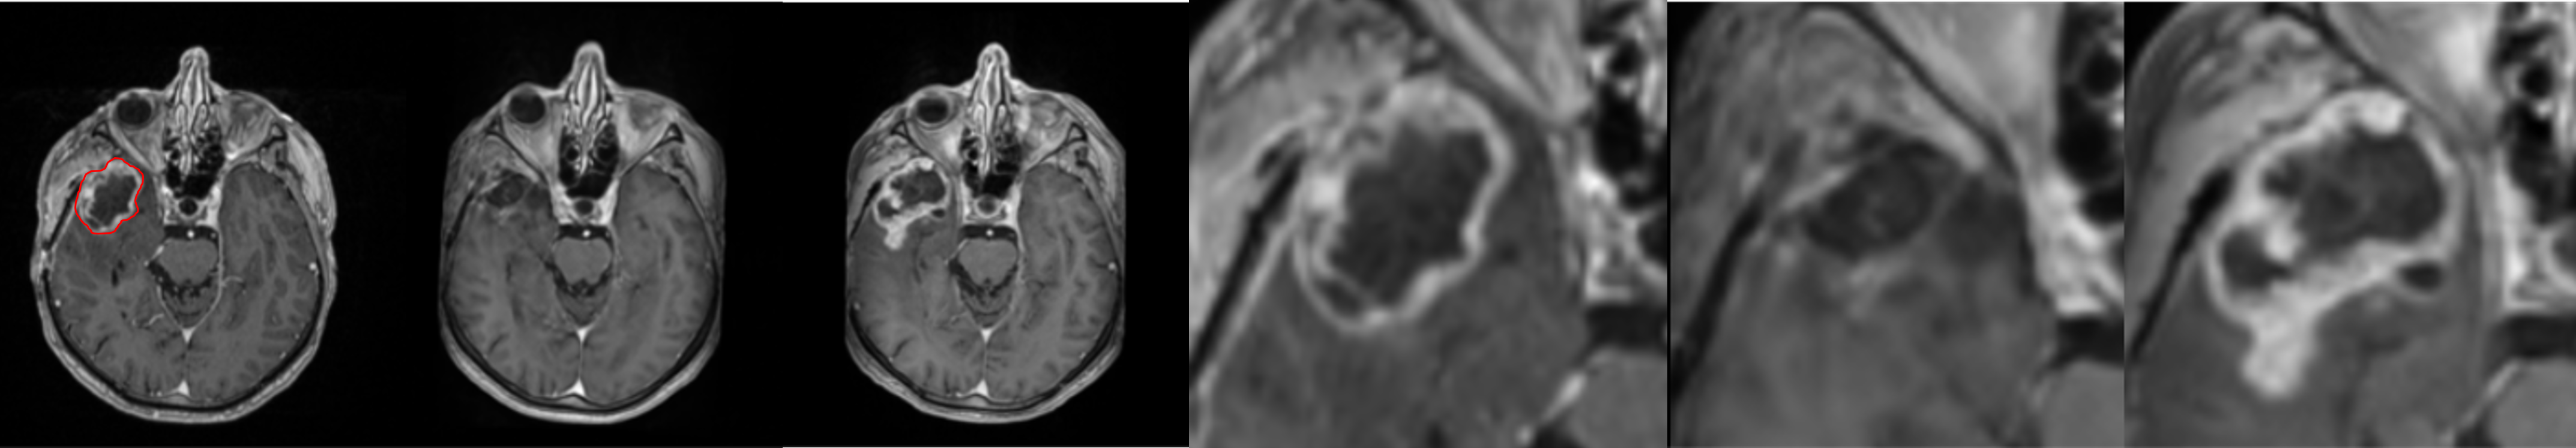

To further illustrate the model’s performance we retained only the pred 2-class model, as it reflects a realistic use case. We present several generated examples in Fig. 4. The first row corresponds to the highest local SSIM score (0.71), depicts a patient who underwent total resection, where tumor progression is minimal. We observe that the model fails to predict the hyper-intensity in the periphery of the tumor (T1-enhancement) in comparison to the ground truth. In contrast, the last row corresponds to the lowest SSIM score (0.02), making it an edge case. We observe that the model generally failed to predict T1-enhancement localized to the tumor area; however, it succeeded in predicting the necrotic area.